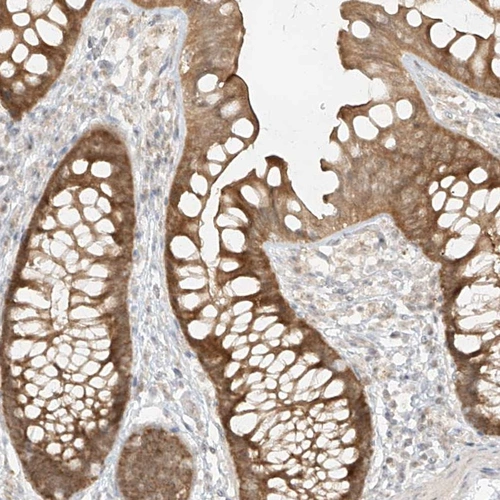

Immunohistochemical staining of human colon shows moderate cytoplasmic positivity in glandular cells.